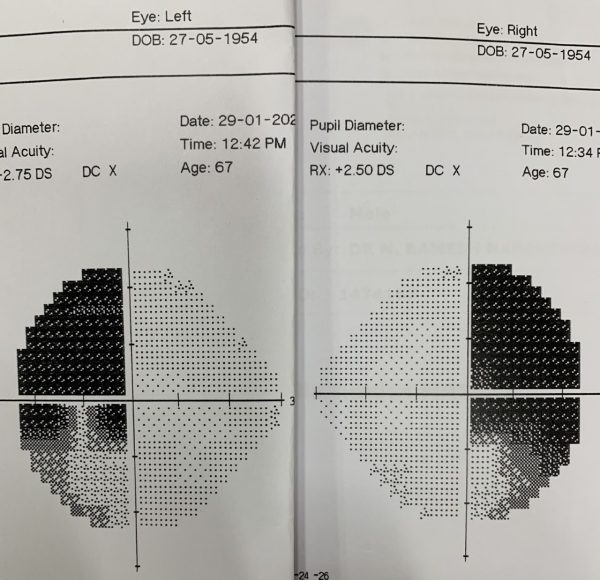

病人简介:董先生,70岁的油棕园园主,因大腺瘤影响视力,造成双侧偏盲。

这颗肿瘤体积是2x2x2.5公分,和细小的脑下垂体比较,显得十分巨大,从磁力共振扫描照片上看到,它刚好长在视神经线的交叉处下方,往上推挤视交叉,造成双眼的外侧上端视野丧失。